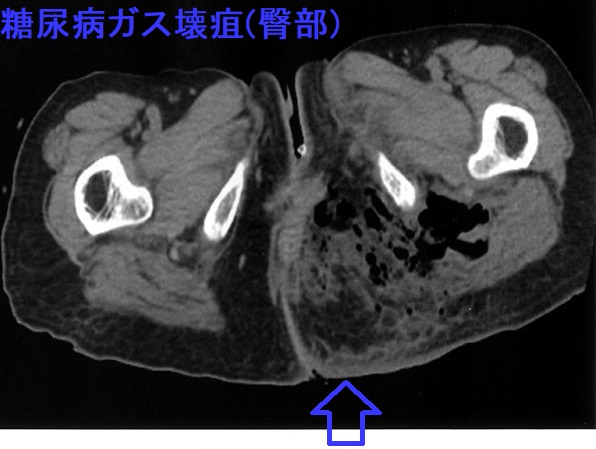

糖尿病ガス壊疽は嫌気性グラム陽性桿菌で芽胞形成するウェルシュ菌感染。気腫性急性化膿性甲状腺炎、生体内毒素型食中毒の原因にも。糖尿病患者ではネコ・イヌ・ウサギの咬み傷・引っ搔き傷にパスツレラ菌が感染し蜂窩織炎・敗血症に。糖尿病足からの破傷風菌(嫌気性菌クロストリジウム・テタニ)感染報告は多く、破傷風毒素による死亡リスクが高い。糖尿病性足壊疽にヨード(ヨウ素)含有軟膏剤(ユーパスタ®;精製白糖・ポビドンヨード軟膏)を長期間使用し急激な甲状腺機能低下症に[急性ヨード(ヨウ素)中毒]。フルニエ壊疽は陰部や肛門周囲のガス壊疽・壊死性筋膜炎。

糖尿病ガス壊疽の最も多い原因はClostridium perfringens(ウェルシュ菌)感染。ウェルシュ菌は、嫌気性のグラム陽性桿菌で芽胞を形成し、

- 糖尿病ガス壊疽を引き起こす。抗生剤が効きやすいはずですが血流が悪い足には十分届きません。